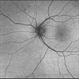

- Unilateral Acute Idiopathic Maculopathy

- chorioretinal inflammations, unilateral acute idiopathic maculopathy, Coxsackie

- Kidron Robertson, Georgia Eye Institute of the Southeast, Savannah, GA

- Infrared photo shows subtle RPE changes on inferior edge of fovea. OCT does not show any significant RPE or IS/OS disruption.